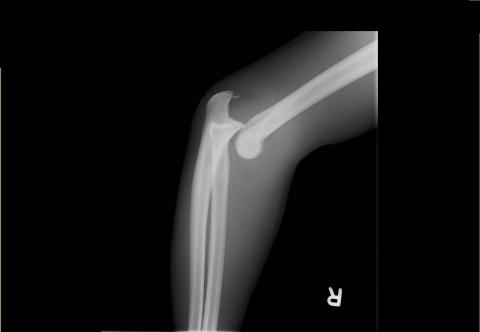

Ellenbogen gebrochen wie lange gips. Die offene Gipsschiene wird durch einen geschlossenen Gipsverband ersetzt. 4 Wochen warscheinlich mindestens. Hierfür wird der Arm in einem Gips ruhiggestellt sodass die beiden Frakturenden wieder zusammenwachsen können.

Für zwei Wochen war ein Gips dran. Normalerweise ist eine Röntgenkontrolle vor der Gipsabnahme Routine. Weigl Die Genesungszeit ist stark von individuellen Umständen abhängig.

In der Regel reicht allerdings bereits eine 1-2 wöchige Ruhigstellung aus bei komplexen Brüchen auch 3-4 Wochen um den Bruch so zu stabilisieren das eine Mobilisation des Gelenkes möglich ist. Am Tag nach der Operation erfolgt eine nochmalige Röntgenkontrolle. Wie lange der Gips getragen werden muss ist in erster Linie von der Schwere der Verletzung abhängig.

6 Wochen eine abschließende Untersuchung statt dann ist die Fraktur in der Regel gut ausgeheilt. Hatte recht lange Schmerzen und auch extrem geschwollenen Arm.